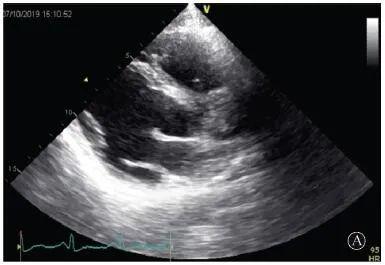

患者入院后無特殊不適,心率70次/min,血壓110/60 mmHg,心功能Ⅱ級。查血常規(guī):血紅蛋白139 g/L,白細胞7.39×109/L,血小板221×109/L。尿常規(guī)、便常規(guī)+潛血均正常。生化:丙氨酸氨基轉(zhuǎn)移酶38 U/L,白蛋白47 g/L,鉀3.9 mmol/L,肌酐(酶法)65 μmol/L,總膽固醇3.52 mmol/L,低密度脂蛋白膽固醇2.08 mmol/L。CK:1256→487 U/L,CK-MB 9.7→3.8 μg/L,cTnI 85.90→68.50 pg/ml。N末端B型利鈉肽原70 pg/ml。CK同工酶電泳:肌酸激酶MM質(zhì)量100.0%(此時CK-MB已正常)。血沉1 mm/第1小時,高敏C反應(yīng)蛋白1.61 mg/L;補體:C3 0.876 g/L,C4 0.174 g/L。免疫球蛋白:IgG 9.52 g/L,IgA 1.73 g/L,IgM 0.62 g/L。血清蛋白電泳未見M蛋白。糖化血紅蛋白5.1%。乳酸(運動前)1.1 mmol/L,乳酸(運動中)6.6 mmol/L,乳酸(運動后)7.8 mmol/L。肌炎抗體譜:抗PM-SCL75(+),余均(-)。心電圖:aVL、V5、V6導聯(lián)T波倒置(圖2)。冠狀動脈CT未見明顯異常。超聲心動圖:左室舒張末內(nèi)徑55 mm,左室收縮功能減低,心尖部、左室壁普遍運動減低,以左室下后壁為著,左室下后壁肌小梁明顯增多可見隱窩,疏松層與致密層之比為1.7;左室射血分數(shù)(雙平面)45%;右冠狀動脈開口6.5 mm,開口處未見明確瘤樣擴張(圖3)。

A:胸骨旁長軸平面,左室舒張末內(nèi)徑略增大,室壁無明顯增厚;

圖3 患者入院后超聲心動圖